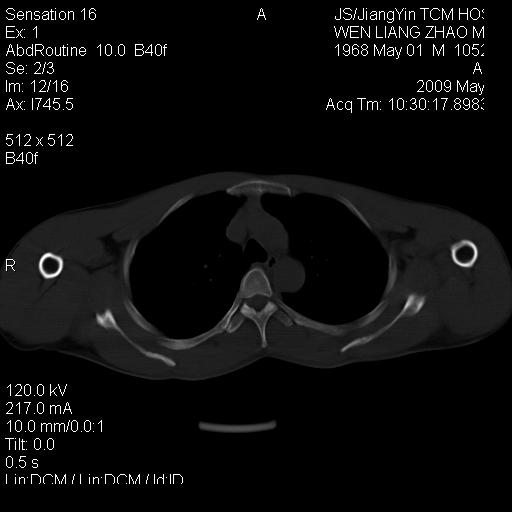

标题: CT19762:左侧喙突处压痛二年。考虑骨样骨瘤。 [打印本页]

标题: CT19762:左侧喙突处压痛二年。考虑骨样骨瘤。

左侧喙突处压痛二年。考虑骨样骨瘤。

病灶外缘膨胀明显,灶缘硬化较少,结合病史较符合骨母细胞瘤,其他亦不排除如软骨及软骨母细胞瘤等(病灶形态,成份较符合,发病部位也符合,只是年龄较大),骨样骨瘤多有较明显的自发性痛,且夜间痛明显,病史为压痛两年,不太符合.

多考虑内生性软骨瘤。年龄及发病部位及病史不支持骨样骨瘤。